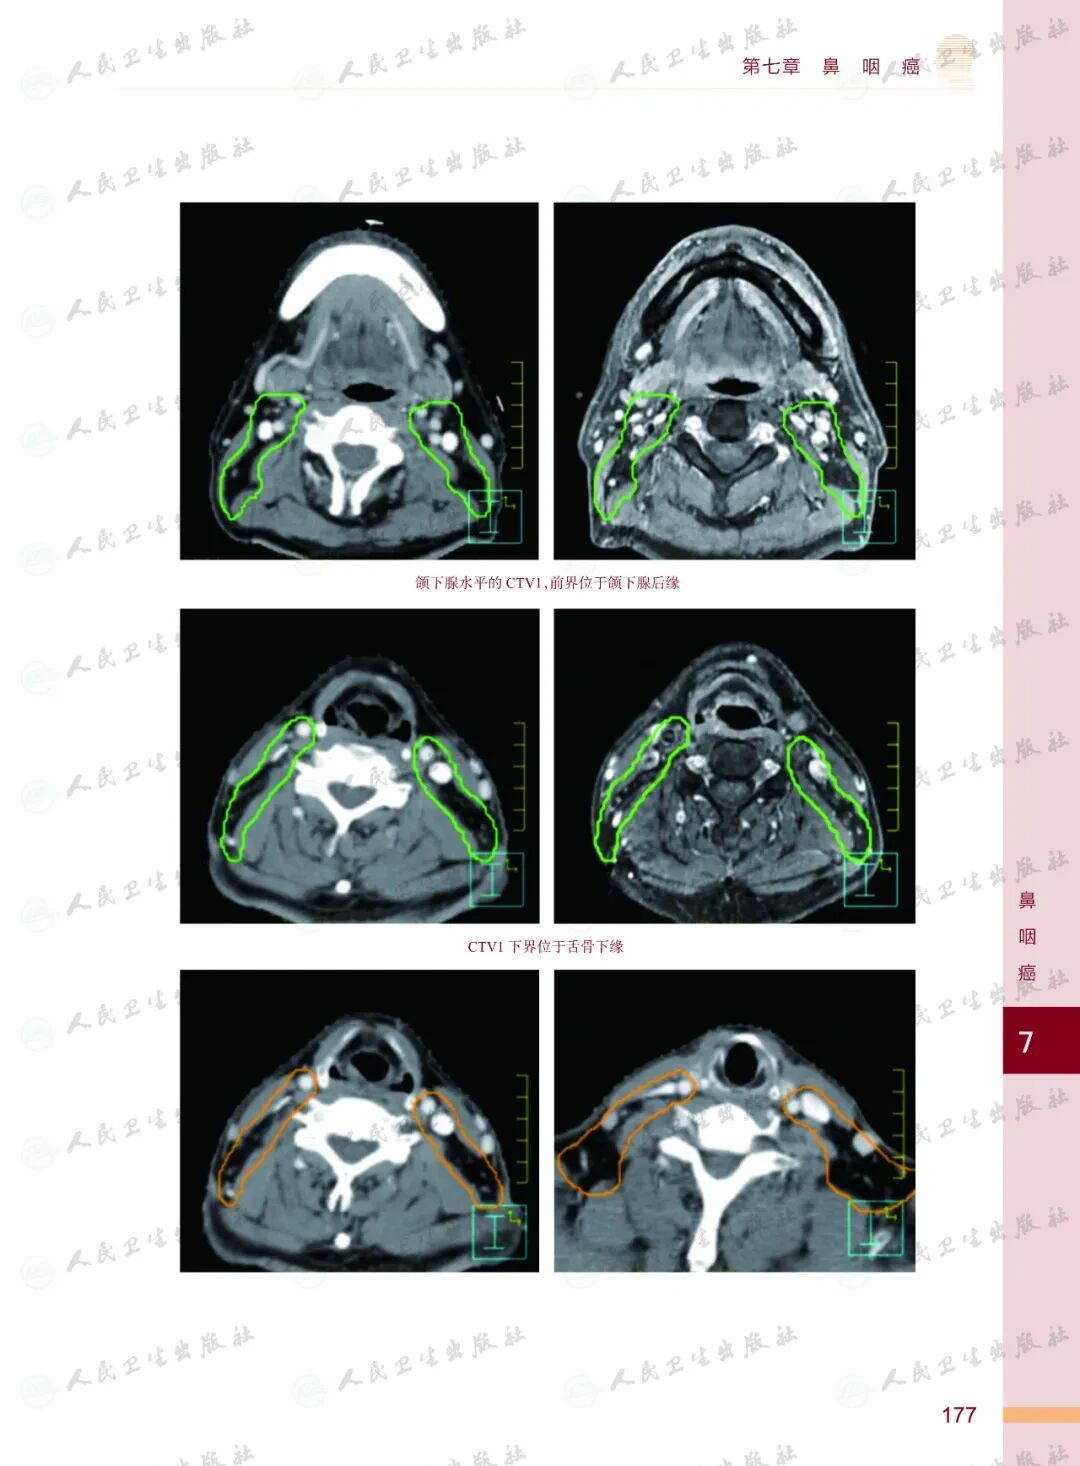

《头颈部肿瘤放射治疗图谱》

——不止是图谱,更是随唤随应的临床良师

样章试读